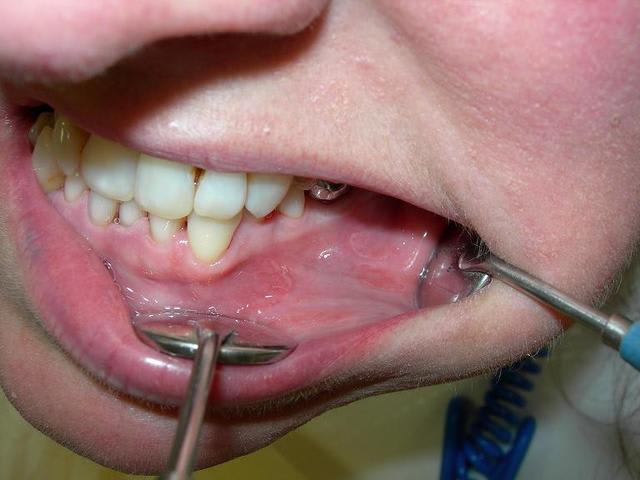

Patiente de 50 ans, ces lésions sont asymptomatiques et présentent dans le vestibule inférieur à D et G, ainsi que dans la zone sublingale.

ça ressemble à un lichen plan